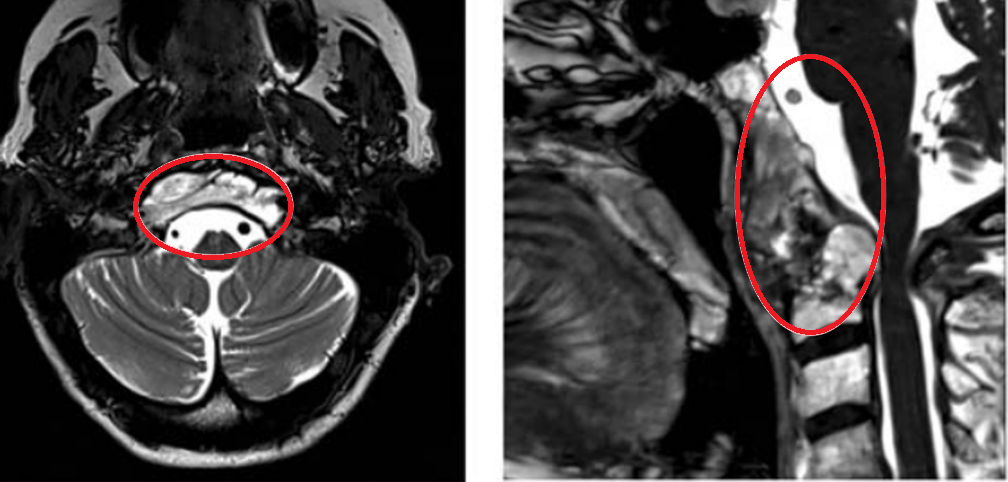

年轻女性因颈部疼痛就诊,MRI发现颅颈交界区脊索瘤,伴骨质破坏和硬膜内延伸,累及双侧椎动脉。

治疗策略:采用内镜辅助的前外侧入路顺利切除肿瘤,术后几天行枕颈融合术确保稳定性。